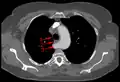

Typisches Bild einer Arteria lusoria in der Computertomographie. (1) Luftröhre, (2) Speiseröhre, dahinter (3) A. lusoria aus dem Aortenbogen entspringend. -